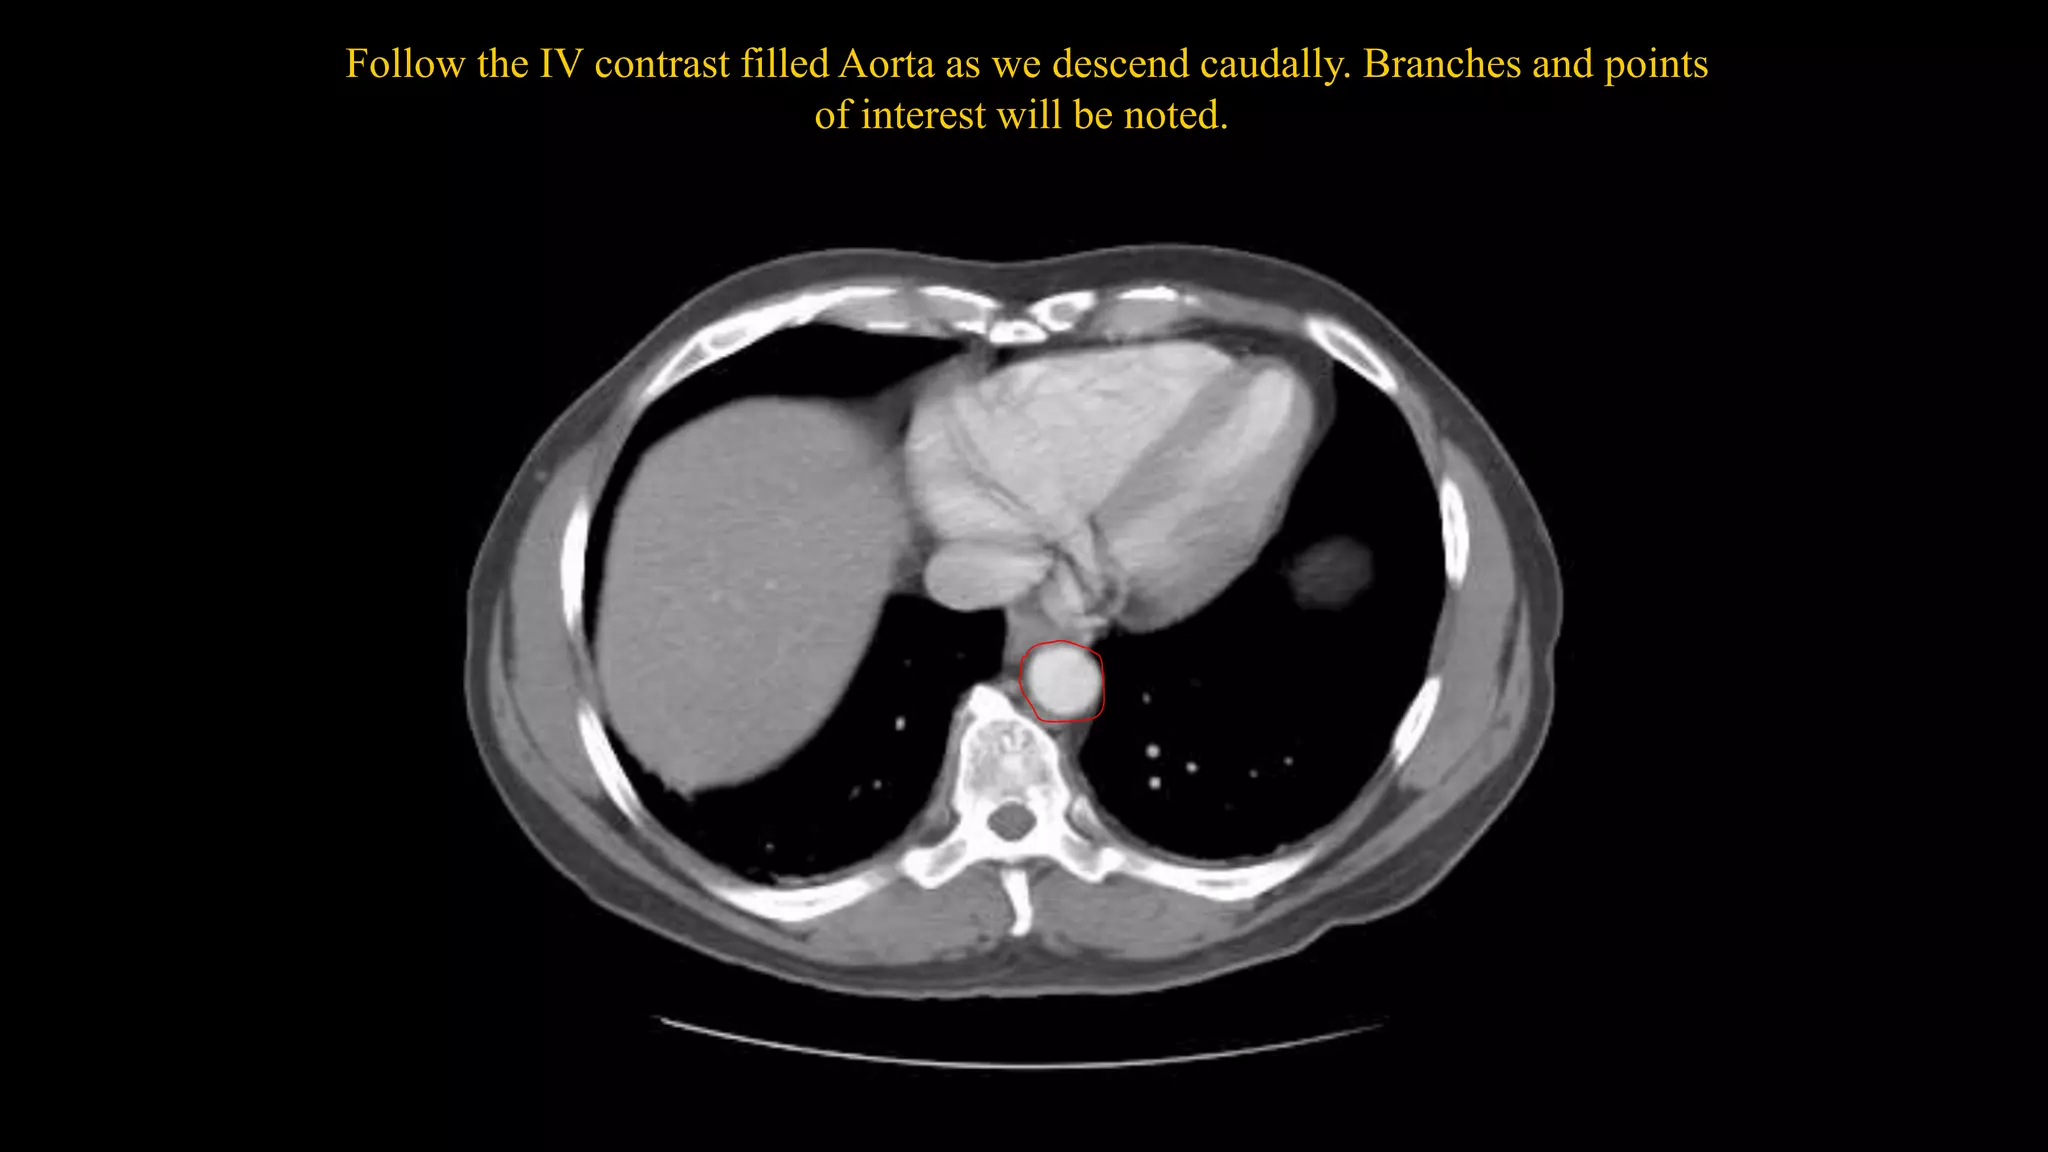

Follow the IV contrast filled Aorta as we descend caudally. Branches and points

of interest will be noted.